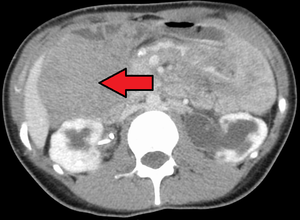

| ورم رباطي كما هو موضح في الاشعة المقطعية | |

الورم الليفي العدواني هو حالة نادرة تتميز بوجود أورام خبيثة . تنشأ الأورام الخبيثة من خلايا تسمى الخلايا الليفية ، والتي توجد في جميع أنحاء الجسم وتوفر الدعم الهيكلي والحماية للأعضاء الحيوية ، وتلعب دورًا مهمًا في التئام الجروح. تميل هذه الأورام إلى الحدوث عند النساء في الثلاثينيات من العمر ، ولكن يمكن أن تحدث لأي شخص في أي عمر. يمكن أن تكون إما بطيئة النمو أو خبيثة. ومع ذلك ، فإن الورم الليفي العدواني عدواني محليًا ويمكن أن يسبب مشاكل تهدد الحياة أو حتى الموت عندما يضغط على الأعضاء الحيوية مثل الأمعاء والكلى والرئتين والأوعية الدموية والأعصاب. معظم الحالات متفرقة ، لكن بعضها يرتبط بداء السلائل الغدي العائلي (FAP). ما يقرب من 10 ٪ من الأفراد الذين يعانون من متلازمة جاردنر ، وهو نوع من FAP مع ميزات خارج القولون ، لديهم أورام رباطية .[1]

يمكن تصنيف الأورام الرباطية على أنها خارج البطن أو جدار البطن أو داخل البطن (الأخير أكثر شيوعًا في مرضى FAP). يُعتقد أن الآفات قد تتطور فيما يتعلق بمستويات هرمون الاستروجين أو الاصابة / العمليات .[citation needed]